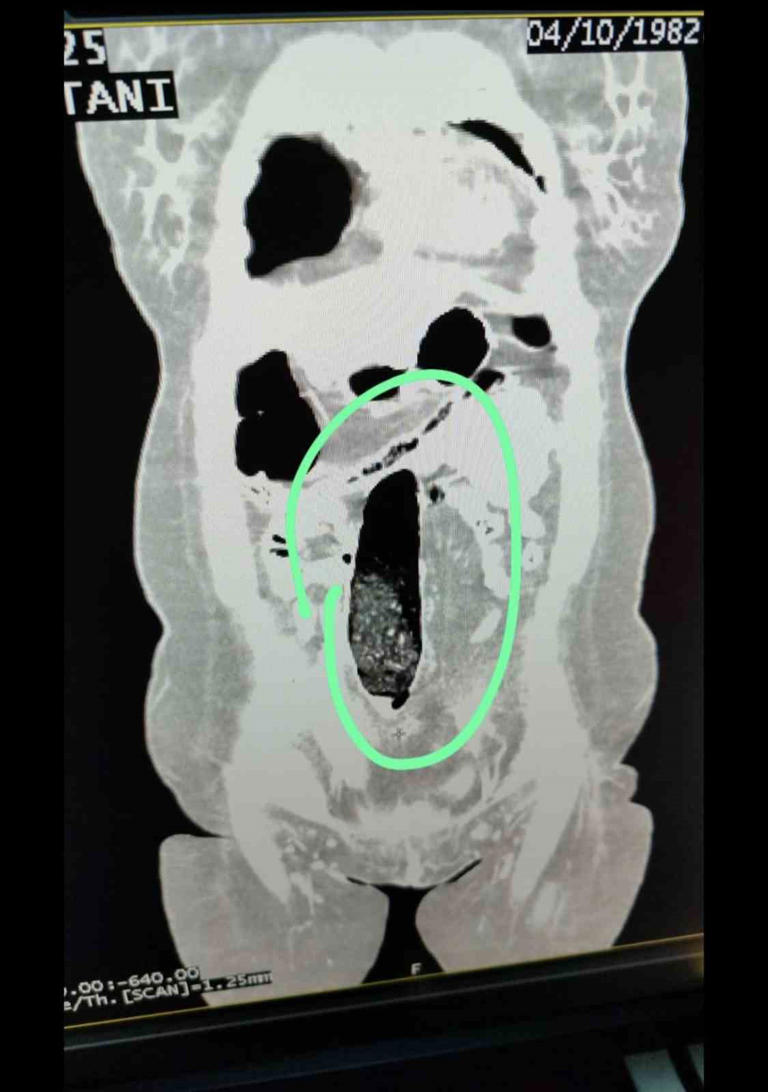

İBu değerlendirme üzerine durdurulan şehirler arası yolcu otobüsünde bulunan 2 İran uyruklu şahıs üzerinde yapılan kontrollerde şüpheli durum tespit edildi. Şahısların iç beden muayeneleri sonucunda, vücutlarının doğal boşluklarında ve bağırsaklarında uyuşturucu madde bulunduğu belirlendi.

Tıbbi müdahale sonucu; F.V. isimli kadın şahıstan 3 parça halinde toplam 397,78 gram metamfetamin, S.İ. isimli erkek şahıstan ise 24 adet sentetik hap ile 3 parça halinde toplam 167,68 gram metamfetamin ele geçirildi.